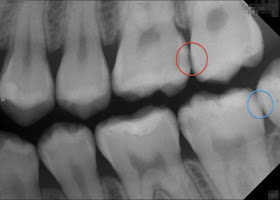

根尖片:紅圈處的牙縫有初期蛀牙,牙冠有黑色陰影。

藍圈處的牙縫沒蛀牙,可看到完整牙冠。

根尖片:約5微西弗。

舉例來說:一位口腔衛生維持得不好、潔牙時,沒有使用牙線清潔牙縫的習慣,而懷疑有肉眼看不見的牙縫間蛀牙時,就會安排根尖片、咬翼片的拍攝。此外,如果有牙齦流血、發炎或是刷牙時,牙齦會流血,經過臨床檢查後懷疑有牙周的問題時,也會安排根尖片的拍攝。